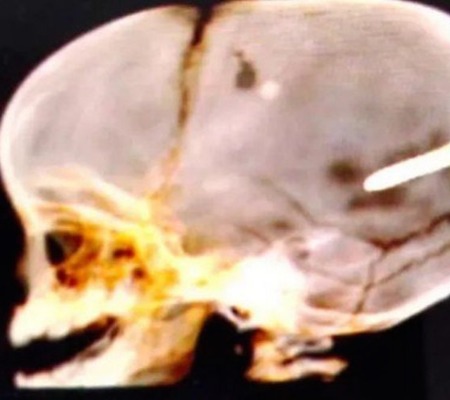

Morreu no fim da tarde desta quarta-feira o bebê de 10 meses atingido na cabeça por um dardo para fixação de gesso, na noite dessa terça-feira, em Paciência, na Zona Oeste do Rio. De acordo com a Polícia Civil, os pais da criança relataram que o filho foi atingido quando estava dentro do carro da família, em uma rua do bairro Gouvea, entre Santa Cruz e Campo Grande, próximo a um local em obras. As informações são do Extra.

Segundo a família, há uma obra próximo ao local em que Wallace foi atingido pelo dardo. O bebê foi levado pelos pais para a UPA Paciencia, onde deu entrada às 22h20 de terça-feira. Em seguida, foi transferido para o Hospital Pedro II. A Secretaria municipal de Saúde informou que Wallace havia passado por uma cirurgia mais cedo para reduzir pressão intracraniana. Não foi possível retirar o objeto, devido à área do cérebro atingida.